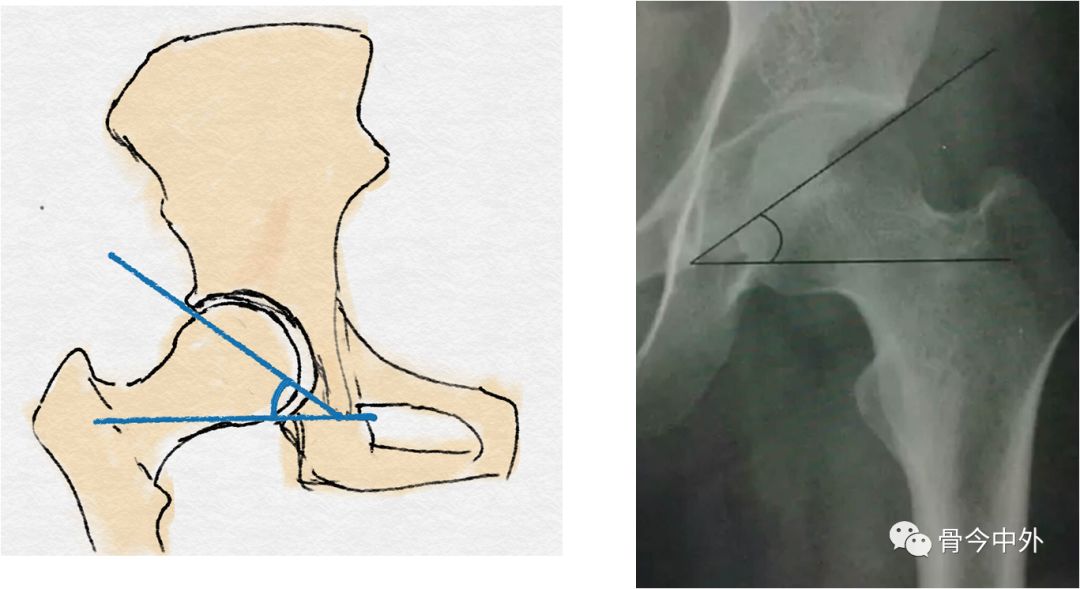

双侧泪滴下缘连线与泪滴至髋臼上缘连线的夹角(正常:33°~38°)

Sharp角:骨盆正位片上,双侧泪滴下缘连线与泪滴下缘和髋臼上缘的连线的夹角,正常35~38度,大于40度可以诊断为髋臼发育不良。